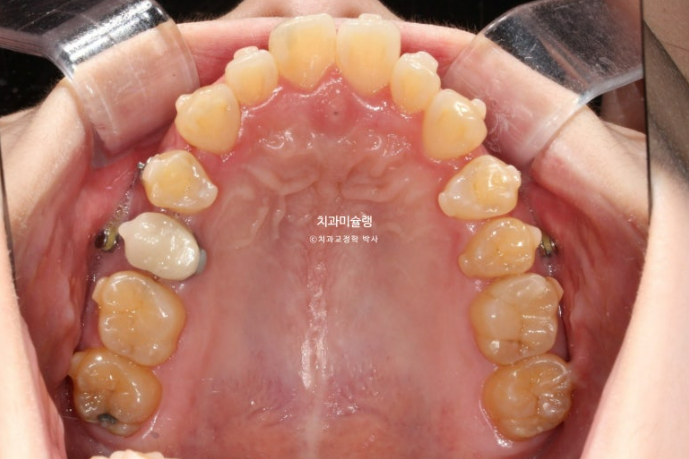

20년 전 교정을 했는데 재발이 되어 재교정을 위해 온 30대 환자분입니다.

24.06

아래 앞니 두 개 잇몸이 유독 내려가 있습니다.

정중선 기준 한쪽만 개방교합이 있는데 한쪽방향으로 혀내밀기 습관때문에 생긴 개방교합일 수 있고 유지장치 변형에 의해 치열이 일그러진 것 일수도 있습니다.

소구치에 윗니와 아랫니가 엇갈려 물리는 가위교합도 보입니다.

큰어금니 교합도 좋은 편 입니다.

파란화살표는 가위교합 원인 치아입니다.